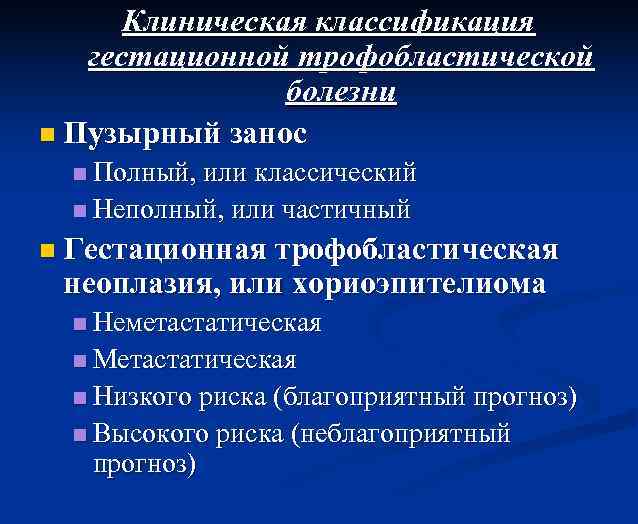

Клиническая классификация гестационной трофобластической болезни n Пузырный занос n Полный, или классический n Неполный, или частичный n Гестационная трофобластическая неоплазия, или хориоэпителиома n Неметастатическая n Метастатическая n Низкого риска (благоприятный прогноз) n Высокого риска (неблагоприятный прогноз)